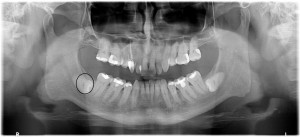

Wisdom teeth (there are 4) become very inflamed and painful when the patient is about 16 years and the jaw has insufficient space for the teeth to come through. Sometimes, these teeth try to force through in the wrong direction, called “impacted wisdom teeth”. This surgery needs great skill and experience and at Caring 4 Smiles, we perform this surgical procedure almost every day. To plan this difficult surgical procedure a Panoramic X-ray ($135) is the minimum for an accurate diagnosis, and sometimes in complex cases (like below), a 3D Cone Beam CT X-Ray ($300) is necessary.

Please see the attached Panoramic X-Rays of one of our patients. This was a very difficult surgery to extract the 2 lower wisdom teeth. Both sites needed large volumes of bone grafting. Had bone grafting not been done, the patient would have had significant post-operative complications due to the unfilled dead space which may or may not have filled over time.